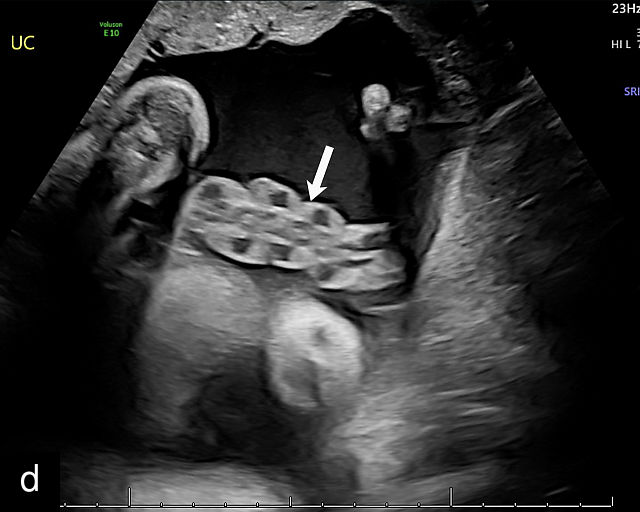

20

(a–c) Grayscale (a) and color Doppler (b,c) ultrasound images of velamentous cord insertion. The cord inserts into the membranes (arrow), from where unprotected fetal vessels (arrowheads) traverse the membranes to insert into the edge of the anterior (a,b) or posterior (c) placenta (p). (d) Color Doppler ultrasound image of velamentous cord insertion, showing the cord inserting into the membranes posteriorly (arrow), from where unprotected fetal vessels (arrowheads) traverse the membranes to insert into the edge of the anterior placenta (p). (e) Ultrasound with color Doppler showing velamentous vessels (arrow) running through the dividing membrane in a dichorionic diamniotic twin pregnancy. The right image shows the placenta after delivery.